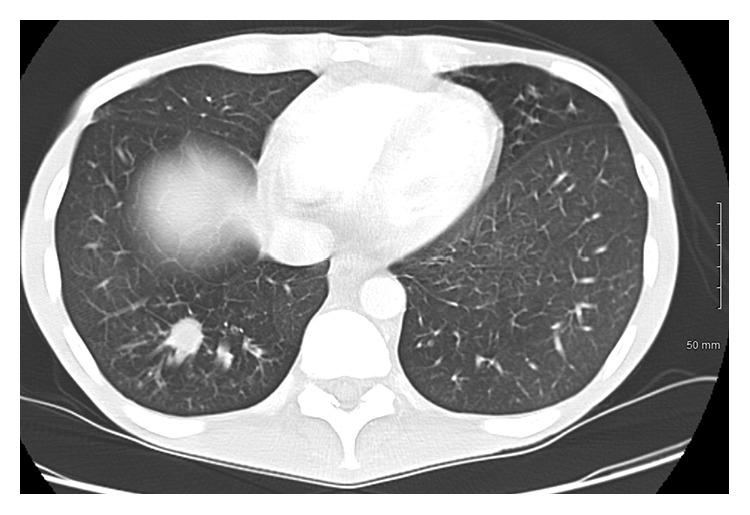

CASE

A 39-year-old male with known, untreated HIV presented to the ED with an acute abdomen after experiencing worsening intermittent abdominal pain for 2 months before that was associated with nausea, vomiting, diarrhea, and weight loss. CT of the abdomen and pelvis revealed evidence of gas in the mesentery, small bowel thickening, edema, and free fluid in the abdomen. Emergency exploratory laparotomy was conducted. Intraoperative findings included a perforated jejunum that was studded with nodular lesions as well as mesenteric masses. Histopathologic exam of these mesenteric masses and jejunal lesions were positive for histoplasmosis.

一名39岁已知未接受治疗的HIV男性患者,在经历了2个月间歇性腹痛加重后,因急腹症就诊于急诊科,腹痛伴有恶心、呕吐、腹泻和体重减轻。腹部和盆腔CT显示肠系膜有气体、小肠增厚、水肿以及腹腔内有游离液体。进行了急诊剖腹探查术。术中发现包括一个布满结节状病变的空肠穿孔以及肠系膜肿块。这些肠系膜肿块和空肠病变的组织病理学检查显示组织胞浆菌病呈阳性。